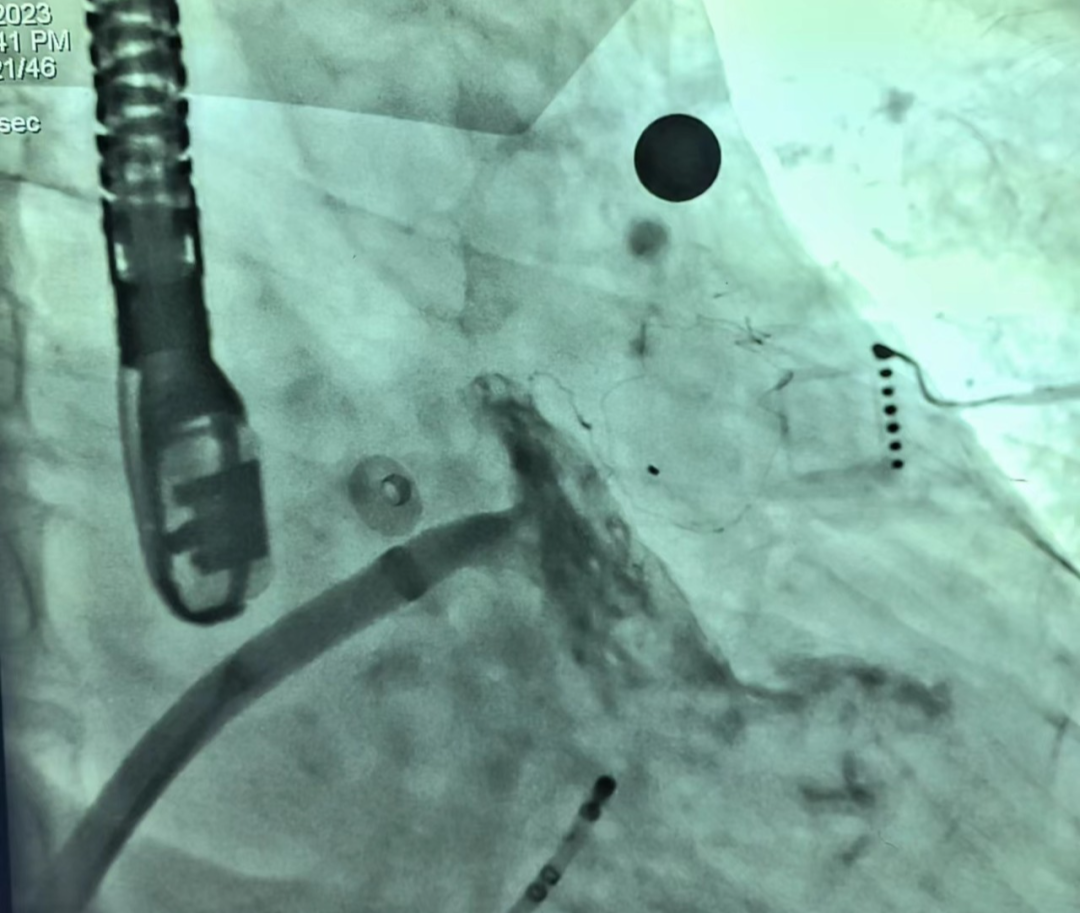

▲术前超声 ▲ 术前造影

结合评估结果和患者及家属意愿,术者团队使用了我国自主研发的Bio-Lefort生物可降解左心耳封堵器,行射频消融+左心耳封堵“一站式”手术。射频消融完成后实施左心耳封堵,封堵器送入后,位置、锚定情况良好,牵拉试验稳定,符合释放原则,遂完全释放封堵器,术后造影示无残余分流,复查超声证实封堵器位置良好,封堵效果理想,手术成功!

▲术后造影